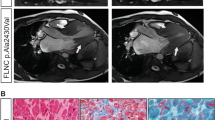

Solubility assays indicated similar localization of desmocollin-2, desmoglein-2, desmoplakin, and junctional plakoglobin in the cell membrane bound insoluble fraction, irrespective of the transfection dosage for both wildtype and mutant TMEM43 (Figure 2A, data not shown for 1:1 dosage). Mutant TMEM43 and lamin B were present in the insoluble nuclear membrane bound fraction (Figure 2B). Although emerin was present in both soluble and insoluble fractions, there was no evident change in the ratio between the two fractions. Immunofluorescence microscopy also showed that TMEM43, lamin B, and emerin were localized to the nuclear membrane in both wildtype and mutant TMEM43 transfected cells (Figure 3). Thus, these data suggest that mutant TMEM43 does not change its own localization or that of its binding partners lamin B and emerin.

Solubility assays. Solubility patterns for (A) desmosomal and (B) nuclear envelope proteins were assessed by immunoblots for soluble and insoluble protein fractions extracted from COS-7 cells transfected with wildtype (WT) TMEM43, mutant (Mut) TMEM43, or a 1:2 ratio of wildtype to mutant (WT + Mut) TMEM43. Sol, soluble fraction containing cytoplasmic (Cyt) proteins; Insol, insoluble fraction containing membrane bound proteins. No differences in solubility patterns were found, suggesting that the presence of mutant TMEM43 did not alter the stability of TMEM43 or of other desmosomal or nuclear envelope proteins.